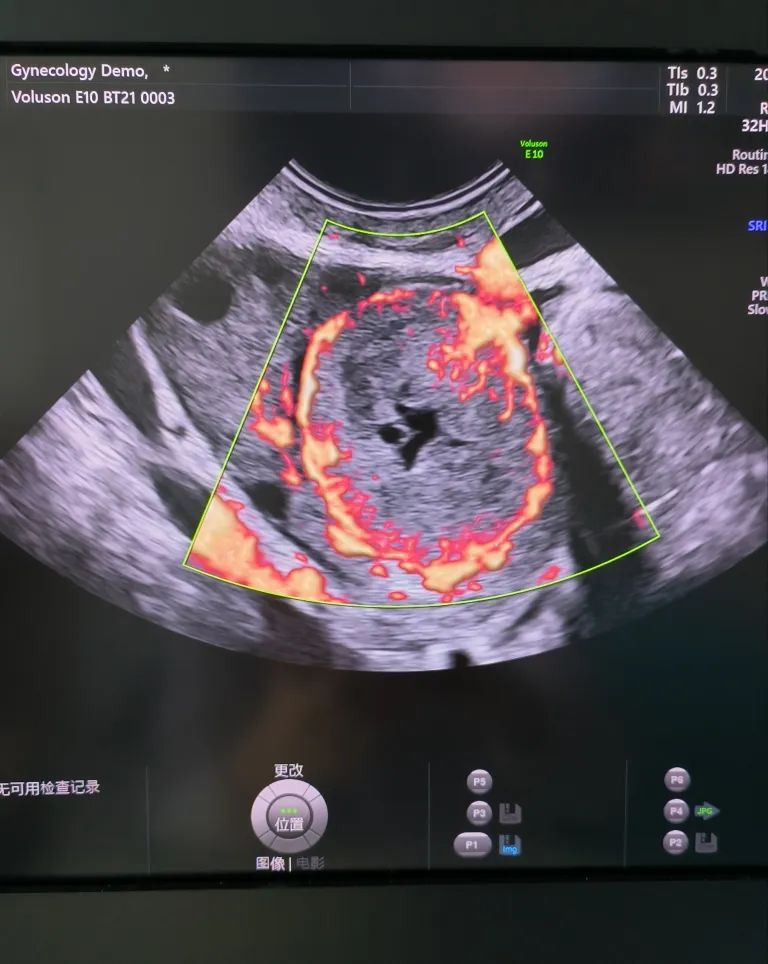

經(jīng)陰道超聲是在陰道超聲探頭上套上避孕套,將探頭伸入陰道進(jìn)行檢查。由于探頭位置接近子宮和卵巢,圖像更清晰,檢查結(jié)果更準(zhǔn)確。而且不需要憋尿,相對(duì)節(jié)省時(shí)間。所以現(xiàn)在大部分醫(yī)院對(duì)有性生活史的婦女更愿意開(kāi)展經(jīng)陰道超聲檢查。